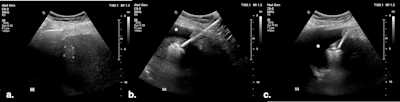

(A) Targeted HCC in segment VIII. (B) Microwave ablation in progress, with artificial ascites (*) separating the liver from the diaphragm. (C) Oblique image compared with the previous one, showing further liver displacement from the diaphragm through mechanical leveraging and illustrating continuous monitoring of the ablation zone. All figures courtesy of Dr. Bruno Di Muzio and Department of Radiology, Alfred Health, Melbourne, and presented at RANZCR's 2024 ASM.

Percutaneous approaches for thermal ablation are commonly guided by ultrasound, CT, or a combination of both, but peripheral liver lesions located near vital organs such as the bowel, stomach, kidneys, gallbladder, diaphragm, and heart -- especially those within 10 mm -- present a challenge due to the risk of collateral thermal injury. The Melbourne group uses several thermo-protective techniques to safeguard these organs and minimize complications.

Artificial ascites involves creating a fluid layer around the liver near the treated area to protect adjacent organs from thermal injury. For hepatic dome tumors, this technique also reduces postprocedure pain caused by diaphragmatic irritation and may create an acoustic window enabling access with ultrasound guidance, the authors pointed out.

Ultrasound-guided puncture at the peritoneal interface uses the liver, gallbladder, or stomach walls as a reference, and a catheter is deployed via a direct method or the Seldinger technique.

Di Muzio and colleagues prefer the 6.3 Fr Dawson-Mueller catheter for creating artificial ascites, but alternatives include a 14-20 G Chiba needle, One-Step Centesis Catheter, or a 5 Fr vascular catheter/sheath. They use a 1 L saline bag with a pressure cuff to expedite the infusion process, and the fluid distribution and liver displacement are monitored with ultrasound. There is no consensus on how thick the layer of fluid separating the structures should be, with the literature reporting between 5 and 10 mm.

This procedure uses a microwave antenna to displace the liver away from at-risk structures, usually in combination with artificial ascites, enhancing the protection of adjacent viscera against thermal injury. It can be useful in patients with adhesions.

"Mechanical displacement technique involves tilting the microwave needle handle to shift the liver away, thereby creating a wider gap between the ablation zone and organs at risk of collateral thermal injury," the authors stated. "When treating cirrhotic livers, which are typically stiff and smaller in volume, leveraging techniques can achieve significant displacement."